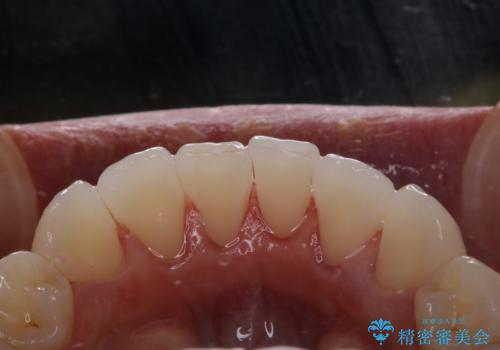

前歯の着色をPMTCできれいに